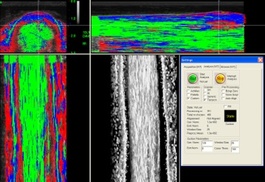

The detailed imagery the UTC can provide about soft tissue health and compromise BEFORE it is injured and needs rehabilitation.

Ultrasound Tissue Characterisation (UTC) technology can differentiate between 4 different fibre types. This enables us to see how many healthy aligned fibres are present, the degree of scar tissue, the severity of a lesion, and the effect of current exercise level on the tendon, all in one scan. This information is essential for preventive screening of tendons (such as prepurchase examinations), pre-race assessments, and post-injury “staging” of the injury to guide rehabilitation.